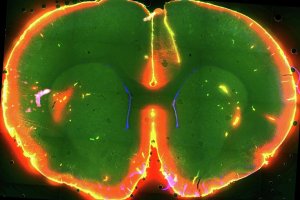

Во сне клетки мозга уменьшаются на 60%, облегчая ликвору перемещение между тканями. При пробуждении клетки увеличиваются, ток жидкости ограничивается.

В мозге во время сна активизируются механизмы "вымывания" отходов — продуктов жизнедеятельности клеток, в чем, возможно, и заключается основная функция сна, эти данные позволят разработать новые методы лечения болезней "грязного мозга", в том числе болезни Альцгеймера, пишут ученые из университета Рочестера (США) в статье, опубликованной в журнале Science.

Ранее группа Недергаард открыла в головном мозге глимфатическую систему — сеть канальцев, по которым быстро циркулирует спинномозговая жидкость (ликвор) вымывающая продукты жизнедеятельности клеток.

Она и ее коллеги в эксперименте с мышами наблюдали за процессами, происходящими в живом неповрежденном мозге с помощью метода двупротонной микроскопии. Как оказалось, у спящих мышей глимфатическая система работает в 10 раз активней. За время сна мозг животных избавляется от бета-амилоида — вещества, накопление которого ведет к болезни Альцгеймера.

Во сне клетки мозга уменьшаются на 60%, облегчая ликвору перемещение между тканями. При пробуждении клетки увеличиваются, ток жидкости ограничивается. В спящем мозге менее активен гормон норадреналин, который отвечает за быструю реакцию на внешние стимулы. Ученые считают, что именно он регулирует сжатие и расширение мозговых клеток в циклах сна-бодрствования.